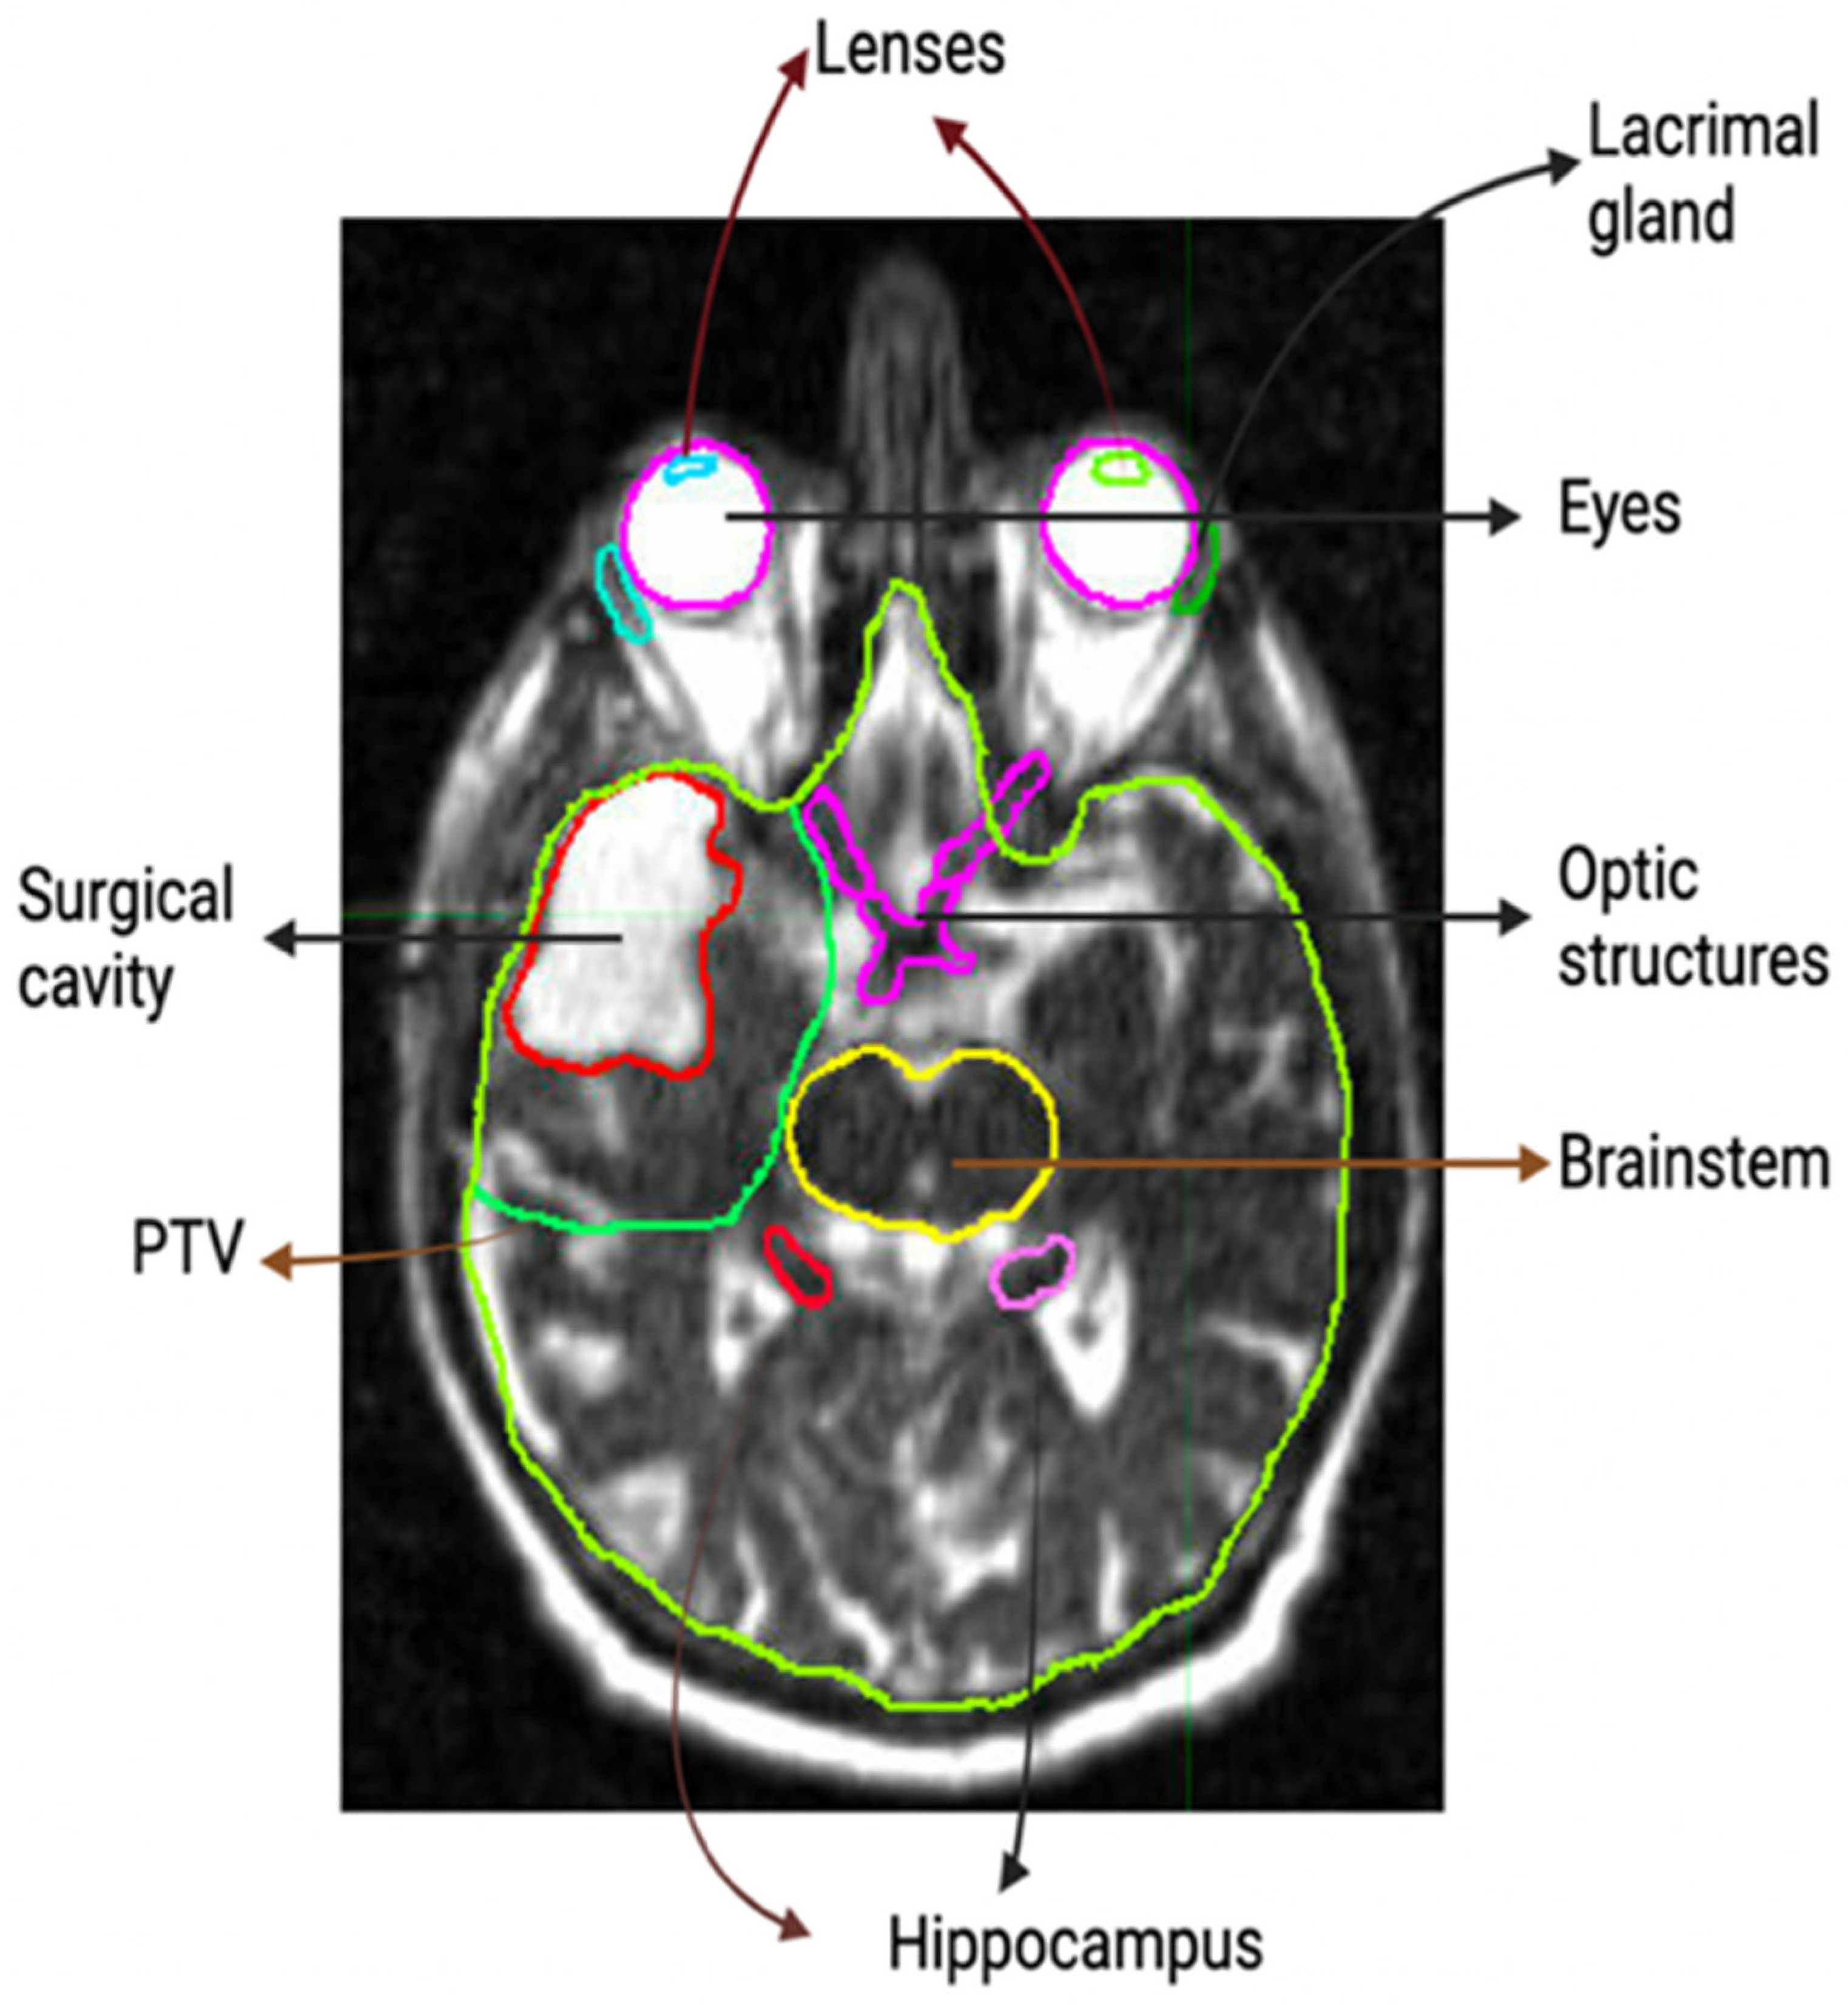

2. Materials and Methods

2.1. Daily Set up Images

2.2. Patient Data Base and Analysis